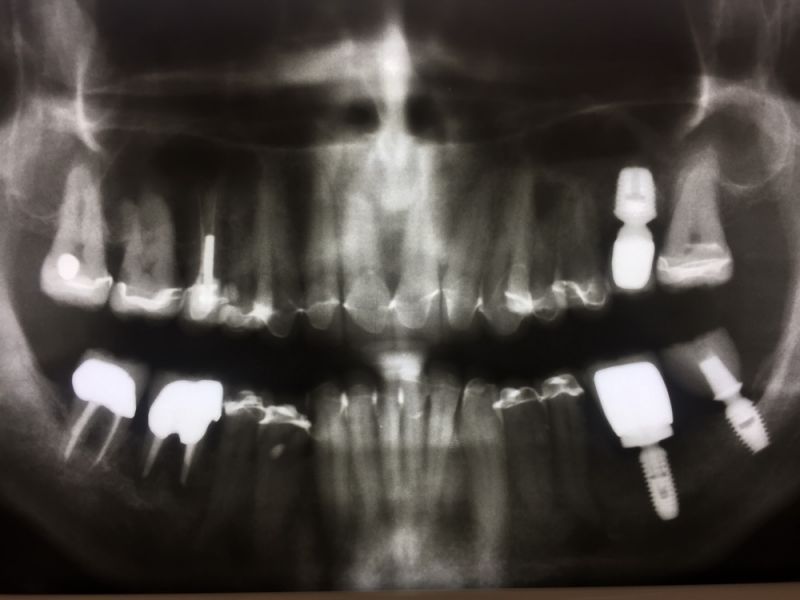

Rekonstruierter CMD Patient aus Kiel erhält zwei neue Kronen

Knappe 13 Jahre ist die Rekonstruktion im Mund. Es werden jetzt zwei Kronen wegen Sekundärkaries ausgewechselt.